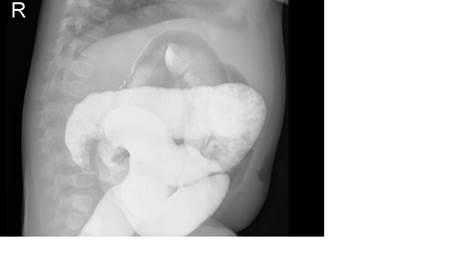

На рисунках 2 и 3 отображена ультразвуковая картина кишечной инвагинации.

На рисунках 4 и 5 представлена картина кишечной инвагинации при рентгенологическом исследовании.

Рис. 4. Ирригограмма при тугом наполнении взвесью сульфата бария - симптом «клешней рака»

Рис. 5. Ирригограмма после опорожнения толстой кишки - симптом «кокарды»